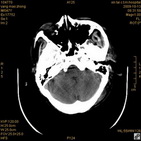

病人杨XX,男,青云街道办事处路踏泉村,住院号51666,CT号:104770。病人因“高血压脑出血”在新泰市人民医院住院治疗5天,治疗效果不佳转入我院,复查CT示左基底节血肿,病人昏迷状态,给予血肿清除术,术后2天复查CT,血肿完全清除,病人恢复好,治疗效果满意。附病人术前术后CT片资料如下。

术前CT

术前CT1 术前CT2 术前CT3 术前CT4